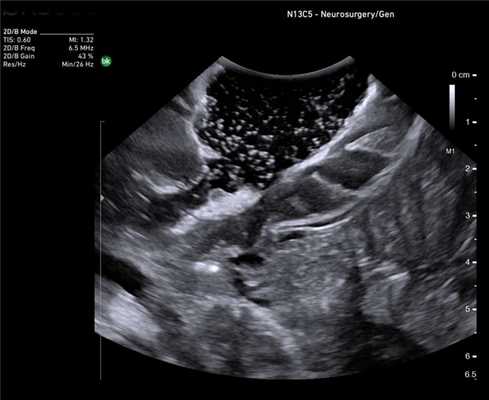

Нейрохирургия

Основная цель хирургического лечения злокачественных опухолей головного мозга - радикальная резекция опухоли при сохранении окружающей функциональной ткани мозга, что напрямую связано с увеличением продолжительности и улучшением качества жизни пациента [12]. Рамочные и безрамочные стереотаксические предоперационные нейронавигационные системы, обычно используются, чтобы помочь хирургам спланировать место краниотомии и идентифицировать критические нервные структуры. К сожалению, эти системы имеют проблемы, связанные с потерей точности в результате искажения, сдвига и деформации после краниотомии и удаления ткани опухоли [13]. В последнее время разработаны новые методы, включая интраоперационную диагностическую визуализацию (Intra-Operative Magnetic resonans) дороги и доступны не во всех нейрохирургический центр. Поэтому большое внимание уделяется возможностям интраоперационного использования УЗИ.

ИОУЗИ помогает локализовать опухоль, определить ее границы, а также провести осмотр зоны после удаления на предмет наличия остаточной опухолевой ткани и оценки радикальности выполненного вмешательства [14,15]. Его основными ограничениями являются пространственное разрешение, ширина и ориентация поля зрения (разные от стандартных ортогональных плоскостей КТ и МРТ) и качества сканирования, которые зависят от оператора.

Отечественные и зарубежные авторы доказали высокий уровень корреляции между данными, полученными при интраоперационном УЗИ и послеоперационной МРТ с контрастным усилением при обнаружении остаточной опухолевой ткани [16,17]. При этом применение режимов допплерографии, а также контрастного усиления значимо повышают информативность исследования. Цветовое допплеровское картирование при сосудистых аномалия позволяет не только локализовать аневризму, но и вместе со спектральной допплерографией провести оценку гемодинамических показателей, например, после клипирования аневризмы.